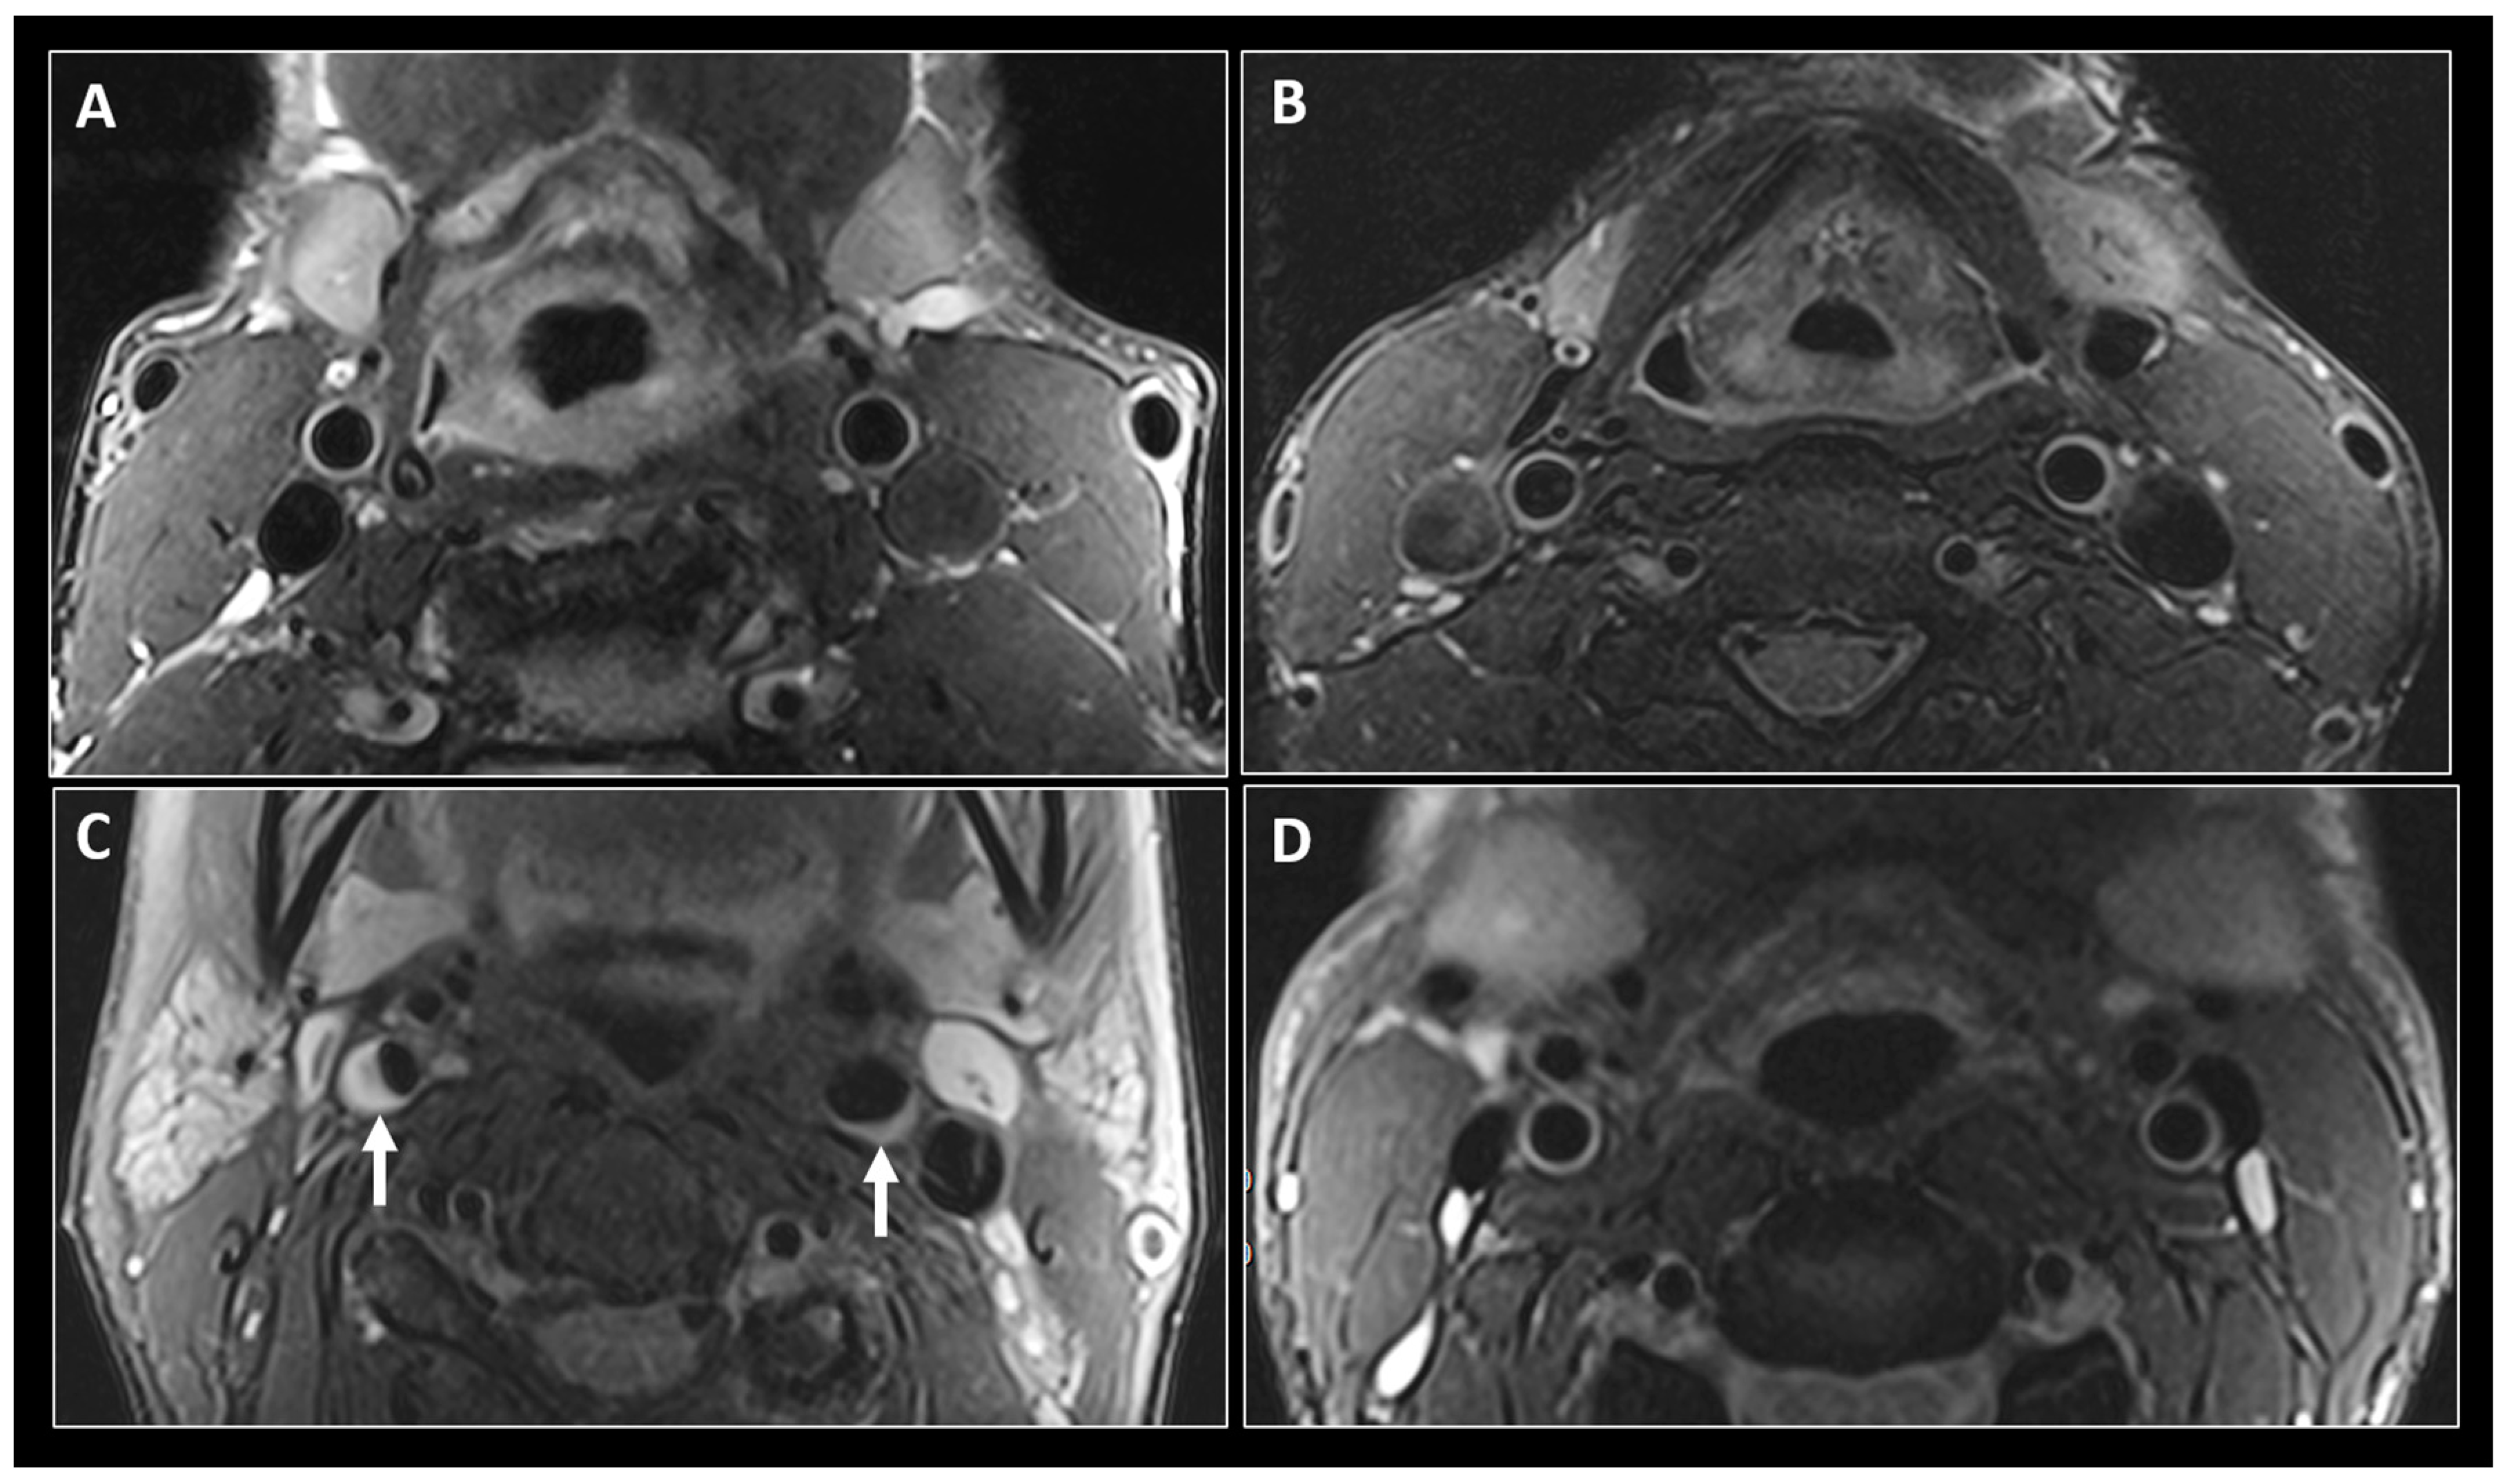

5. Magnetic Resonance Rmaging (MRI)

- Labounty, T.M.; Hardy, W.D.; Fan, Z.; Yumul, R.; Li, D.; Dharmakumar, R.; Conte, A.H. Carotid artery thickness is associated with chronic use of highly active antiretroviral therapy in patients infected with human immunode fi ciency virus: A 3.0 Tesla magnetic resonance imaging study. Br. HIV Assoc. 2016, 17, 516–523. [Google Scholar]

- Mee, T.C.; Aepfelbacher, J.; Krakora, R.; Chairez, C.; Kvaratskhelia, N.; Smith, B.; Sandfort, V.; Hadigan, C.; Morse, C.; Hammoud, D.A. Carotid magnetic resonance imaging in persons living with HIV and 10-year atherosclerotic cardiovascular disease risk score Short communication Carotid magnetic resonance imaging in persons living with HIV and 10-year atherosclerotic cardiovascular diseas. Antivir. Ther. 2018, 23, 695–698. [Google Scholar] [CrossRef]

- Rose, K.A.M.; Vera, J.H.; Drivas, P.; Banya, W.; Pennell, D.J.; Winston, A. Europe PMC Funders Group Atherosclerosis is evident in treated HIV-infected subjects with low cardiovascular risk by carotid cardiovascular magnetic resonance. J. Acquir. Immune Defic. Syndr. 2016, 71, 514–521. [Google Scholar] [CrossRef]

- Fayad, Z.A.; Fuster, V.; Fallon, J.T.; Jayasundera, T.; Worthley, S.G.; Helft, G.; Aguinaldo, J.G.; Badimon, J.J.; Sharma, S.K. Noninvasive In Vivo Human Coronary Artery Lumen and Wall Imaging Using Black-Blood Magnetic Resonance Imaging. Circulation 2000, 102, 506–510. [Google Scholar] [CrossRef]

- U-king-im, J.M.; Trivedi, R.A.; Sala, E.; Graves, M.J.; Higgins, N.J.; Cross, J.C.; Hollingworth, W.; Coulden, R.A.; Kirkpatrick, P.J.; Antoun, N.M.; et al. Evaluation of carotid stenosis with axial high-resolution black-blood MR imaging. Eur. Radiol. 2004, 14, 1154–1161. [Google Scholar] [CrossRef]

- Saam, T.; Habs, M.; Buchholz, M.; Schindler, A.; Bayer-karpinska, A.; Cyran, C.C.; Yuan, C.; Reiser, M.; Helck, A. Expansive arterial remodeling of the carotid arteries and its effect on atherosclerotic plaque composition and vulnerability: An in-vivo black-blood 3T CMR study in symptomatic stroke patients. J. Cardiovasc. Magn. Reson. 2016, 18, 11. [Google Scholar] [CrossRef]

- Ripa, R.S.; Knudsen, A.; Hag, A.M.F.; Lebech, A.; Loft, A.; Sune, H. Feasibility of simultaneous PET/MR of the carotid artery: first clinical experience and comparison to PET/CT. Am. J. Nucl. Med. Mol. Imaging 2013, 3, 361–371. [Google Scholar]

- Floris-moore, M.A.; Fayad, Z.A.; Berman, J.W.; Schoenbaum, E.E.; Klein, R.S.; Weinshelbaum, K.B.; Fuster, V.; Howard, A.A.; Lo, Y.; Schecter, D. Association of HIV Viral Load with Monocyte Chemoattractant Protein-1 and Atherosclerosis Burden Measured by Magnetic Resonance Imaging. AIDS 2010, 23, 941–949. [Google Scholar] [CrossRef]